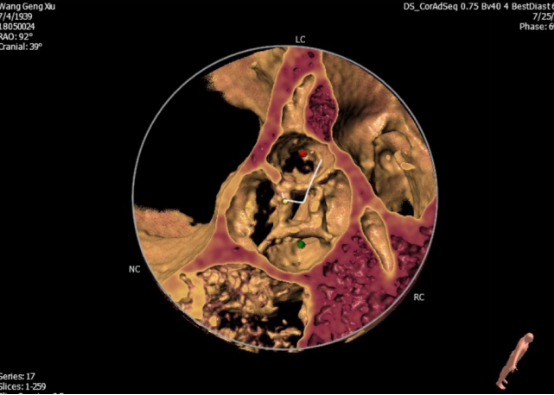

术前通过CT检查,计算机模拟重建的主动脉瓣图像,显示患者为四叶主动脉瓣畸形,并伴有严重的关闭不全。